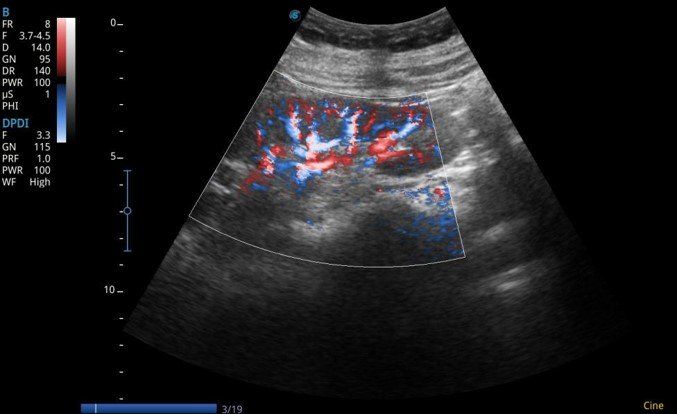

- Farbdoppler (Dynamic Color Technologie) Triplex, PW

- Direktionaler Powerdoppler